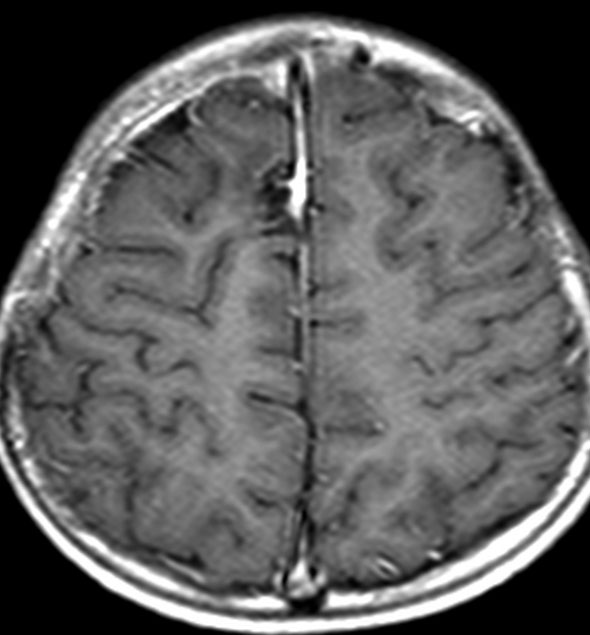

放射線治療がほとんど効かなかった例(高悪性度グリオーマに類似するもの)

手術で簡単にとれそうなPNETです。実際に全摘出していただいて,すぐに脳脊髄照射と腫瘍床照射54グレイの放射線治療を受けたのですが,放射線治療最中に手術摘出した場所から再発してしまいました。再手術で摘出して,シスプラチンを基剤とした併用化学療法やテモゾロマイドを使いましたが,間もなく激しい脳脊髄播種を生じました。MIB-1は70%で,膠芽腫のように強いanaplastyがありました。

放射線治療が最も強力な治療手段なのですが,全く無効なPNETがあります。